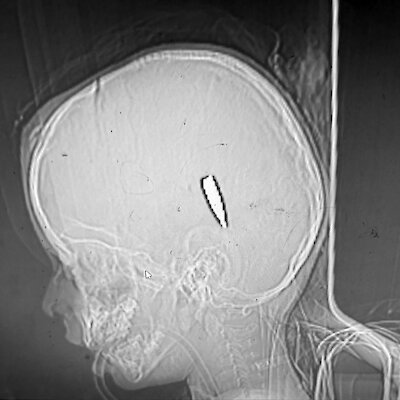

De Volkskrant przedstawił dwóm patologom sądowym dziesiątki zdjęć dzieci z ranami postrzałowymi oraz różne zdjęcia rentgenowskie. Potwierdzili oni, że rany zostały spowodowane przez pociski, a nie odłamki granatów. „Najprawdopodobniej chodzi o strzały oddane z dużej odległości, wymierzone w głowę i/lub szyję, przy użyciu amunicji wojskowej” – komentuje patolog sądowy Wim Van de Voorde, emerytowany profesor Uniwersytetu w Leuven. Według Van de Voorde zdjęcia nie są wystarczającej jakości, aby wyciągnąć wnioski prawne, „co jest zrozumiałe, biorąc pod uwagę bardzo trudne warunki lokalne”.

Patolog sądowy Frank van de Goot: „Na zdjęciach rentgenowskich widzę głowy dzieci z kulami w środku. Kule musiały stracić dużo energii po drodze, bo dzieci mają cieńsze czaszki niż dorośli, bo inaczej przeszłyby na wylot. Tak więc do tych dzieci strzelano z dużej odległości.

Wynik ten jest zgodny z zeznaniami naocznych świadków, którzy opisali lekarzom, że kule były zazwyczaj wystrzeliwane przez uzbrojone drony lub snajperów izraelskiej armii (IDF). Snajperzy mogą z dużej odległości, czasami nawet ponad tysiąca metrów, określić, kogo chcą trafić i gdzie. IDF nie chciała odpowiadać na pytania dotyczące strzelania do dzieci przez snajperów.

Według byłego dowódcy sił lądowych Marta de Kruifa prawdopodobieństwo, że były to przypadkowe trafienia, jest zerowe, ponieważ lekarze opisują ponad sto przypadków. „Proszę pomyśleć, jaką powierzchnię głowy zajmuje w stosunku do całego ciała. Jeśli ma się wiele ran postrzałowych w okolicy serca i głowy, nie jest to przypadkowe uszkodzenie. Jest to naprawdę celowy ostrzał”.